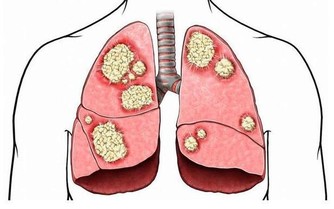

一、腦出血類

長期高血壓、動脈粥樣硬化都可能引發腦出血,造成偏癱、昏迷甚至死亡。